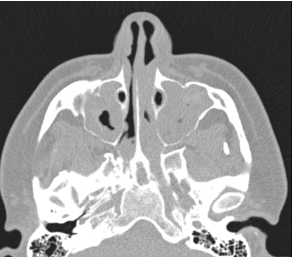

A 26-year-old male with chronic sinusitis presented to clinic for evaluation of nasal crusting and bloody discharge (Image 1). He had a history of nasal polyposis resection. Laboratory evaluation was significant for leukocytosis and mild anemia. CXR showed nonspecific multifocal patchy infiltrates. Chest CT revealed numerous bilateral pulmonary nodules with central cavitation (Image 2). Immunological testing revealed the presence of c-ANCA and proteinase 3 (PR3) antibodies. GPA was suspected and the patient was started on prednisone. Bronchoscopy showed friable nasal mucosa with cobble stoning. Infectious workup was negative. He was initiated on high dose steroid with a plan to add rituximab (RTX). Few days later, he presented with chest pain, he was hypertensive and tachycardiac, he had elevated BNP and troponin. EKG showed no ST changes, but Echocardiogram revealed an EF of 50% with dilated left ventricle. Coronary vasculitis was suspected, cyclophosphamide (CYC) induction was initiated. Cardiac MRI demonstrated moderate systolic dysfunction with EF 34% and atypical myocarditis. Left heart catheterization (LHC) revealed disseminated vasculitis with diffuse involvement of distal coronary arteries. He was initiated on guideline-directed medical therpay and given RTX. A week later, he presented with elevated creatinine. Renal biopsy revealed ANCA-mediated focal crescentic glomerulonephritis. He underwent plasmapheresis with imporvement of his kidney function. A month later, he presented with recurrence of chest pain. Troponins were elevated, EKG demonstrated inferior ST elevation, and LHC revealed progression of coronary vasculitis. Repeat echocardiogram showed an EF of 15%. He was treated with steroids, and CYC. However, he continued to worsen, and eventually progressed to cardiogenic shock with multiorgan failure and was put on VA-ECMO support. The patient was transferred to a higher level of care center for LVAD and heart transplant.